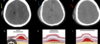

No que consiste um hematoma epidural?

Sangramento originado em região epidural (extradural) - acima da dura mater Terá formato biconvexo (bucho) na TC que não ultrapassa suturas - Fica colado no crânio!

No que consiste um hematoma subdural?

Sangramento originado no espaço subdural Na TC terá aspecto côncavo e convexo (foice) - costuma ultrapassar suturas

38

Como saber se um hematoma subdural é agudo ou crônico?

Quando suspeitar de hematoma epidural apenas pela clinica do paciente?

Intervalo Lúcido! 1º Perde a consciência 2º Recobra consciência 3º Perde consciência novamente Ou Ele é atendido de forma consciente e depois perde a consciência!

43

Qual o principal vaso acometido após um hematoma extradural?

Arteria meningea média

44

Qual o principal vaso acometido após um hematoma subdural?

Plexo venoso - Veias ponte